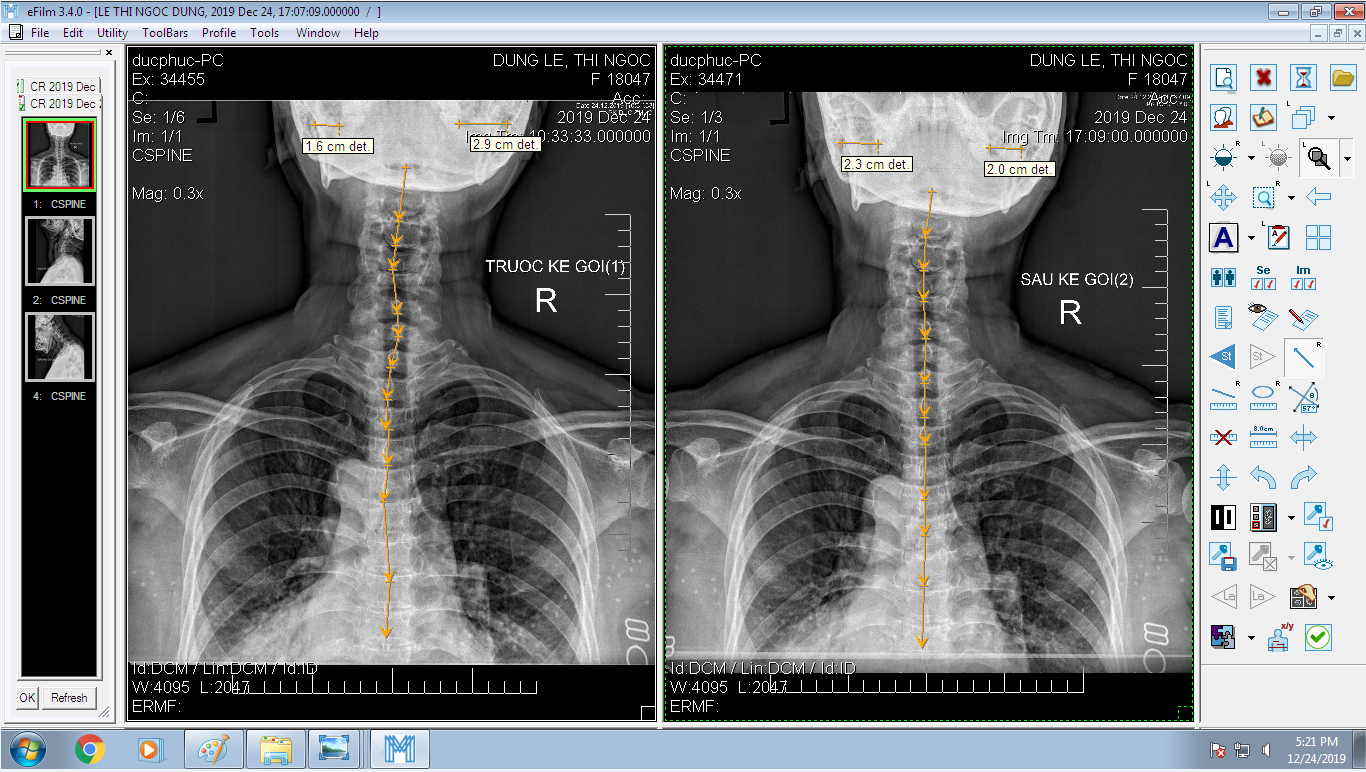

DOCTORLOAN đã thành công trong điều chỉnh xương khớp về đúng vị trí trong thời gian ngắn